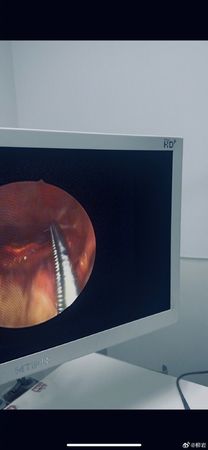

▲柳岩喝湯卡魚刺就醫。(圖/翻攝自柳岩微博)

從柳岩公開的內視鏡畫面中可見,醫師使用專業器械從喉嚨中精準夾出魚刺過程。而她本人事後也附上一張在車上的自拍照,面色略顯疲憊。她透露是因為喝了自己煮的鯽魚湯所導致,「愛喝,以後不喝了。」